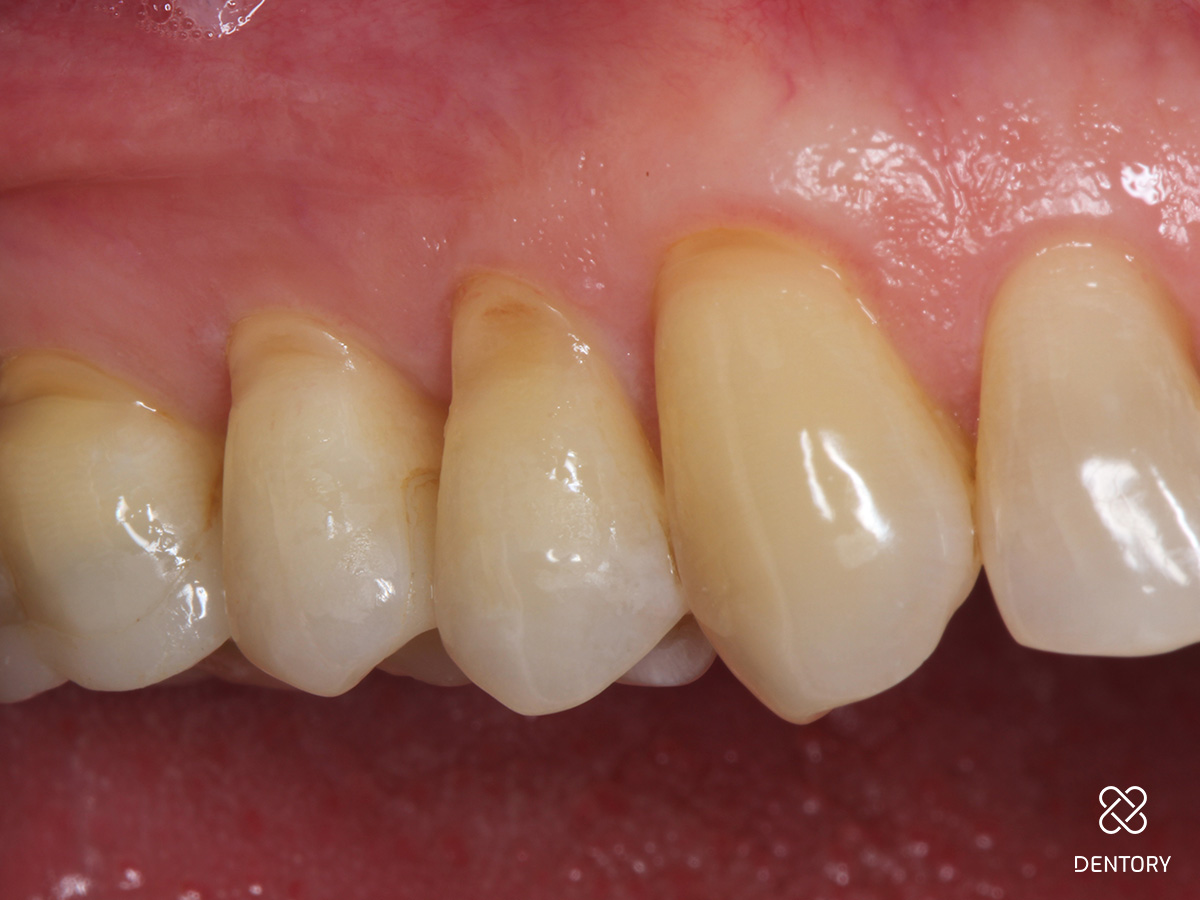

Abbildung 3

Zunächst Beläge und Biofilm sauber entfernen. Um eine Blutung des umgebenden Gewebes zu verhindern, wird ein Gingiva Schutzhalter angelegt. Das Instrument lässt sich schnell individuell anpassen und dem Zahnhals entsprechend formen. Die Gingiva wird leicht nach unten geschoben, um einen perfekten Sitz des Instrumentes zu garantieren.